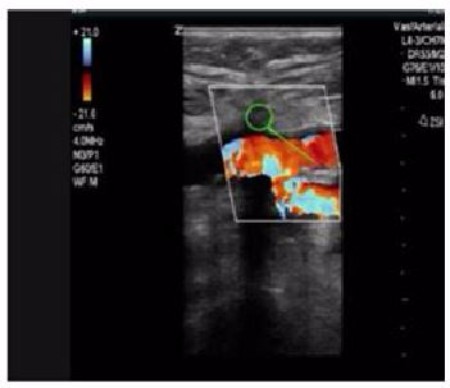

Celt ACD® is located in the arterial wall not in the circulation.

Puncture sites closed by Celt ACD® are completely healed at five weeks or less and covered by endothelium.

Celt ACD® (indicated by the green circle above) is in the arterial wall and not in the circulation as seen on ultrasound of bifurcation of femoral artery.